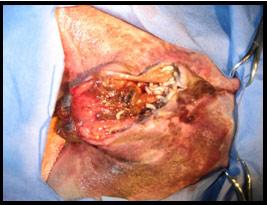

Le diagnostic est facile à établir. Il se fait par visualisation des miases sur la peau ou dans une plaie.

Il faut d’abord raser et nettoyer la plaie puis d'en retirer les larves. Au besoin, si l’état du chien le permet, un débridement (nettoyage) de la plaie sous anesthésie est la méthode la plus efficace pour éliminer les larves.